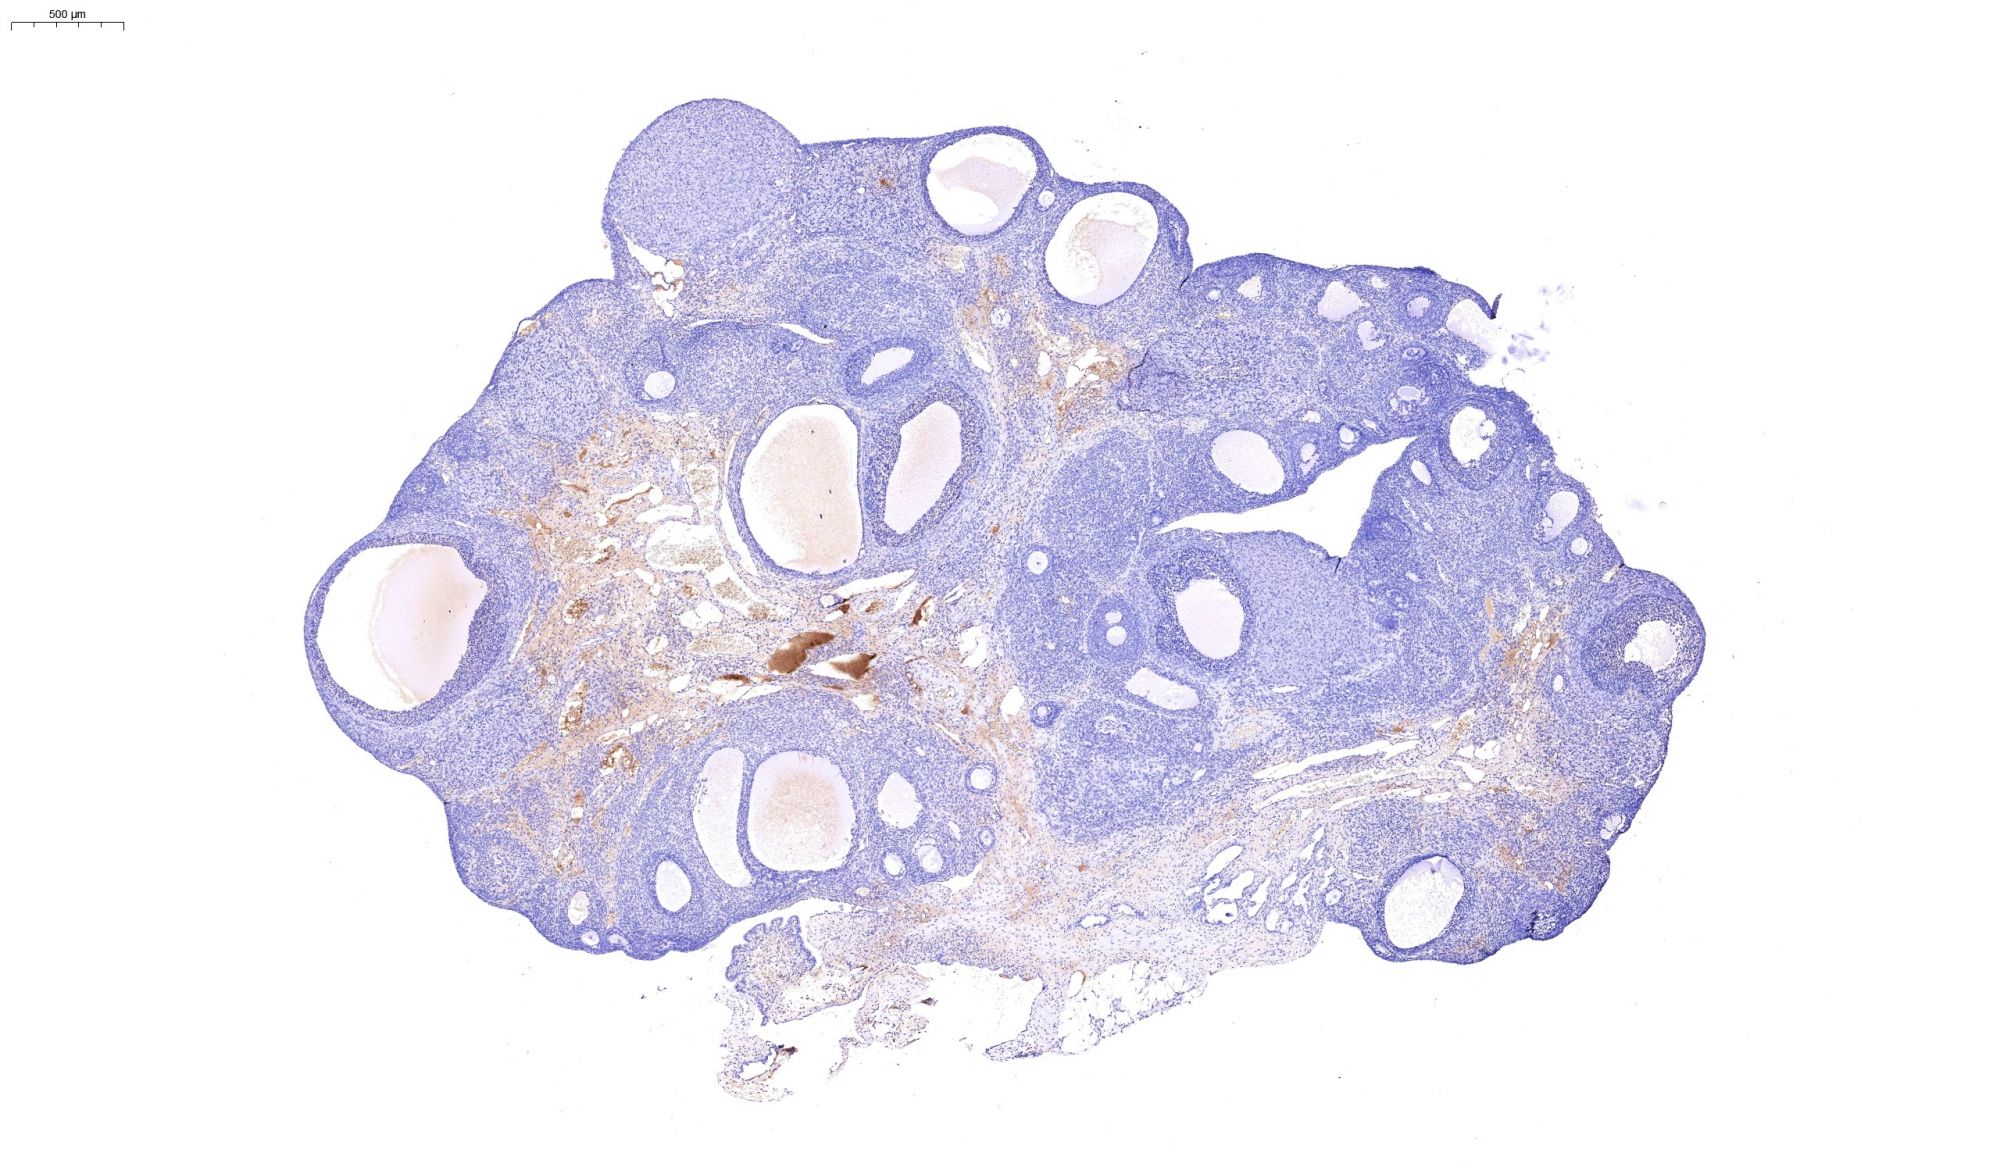

免疫組化染色-卵巢

IHC免疫組化

892